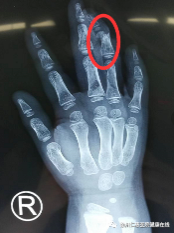

术前(左图)术后(右图)

齐伟亚、熊祖国手术团队先为俊俊的伤处进行了清创处理,然后把环指的骨折复位固定,找到损伤的血管神经并接上,2小时手术顺利结束。

手术是在显微镜下进行,五岁小孩的指侧血管直径不到0.2毫米,2小时的手术过程中,手术视野的直径也不过5公分,缝合用的线比头发还要细得多,非常考验医生的细致与耐心。